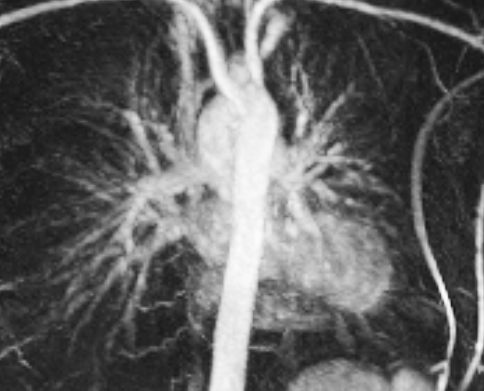

These MRI scans will help the research team evaluate the amount of air getting to different parts of the lungs and the blood supply to the lungs in healthy people and then compare these values with those found in patients. The aim eventually is to develop a way of monitoring lung disease progression in patients without requiring the use of CT scans or X-rays (which carry dangers from repeated radiation exposure).